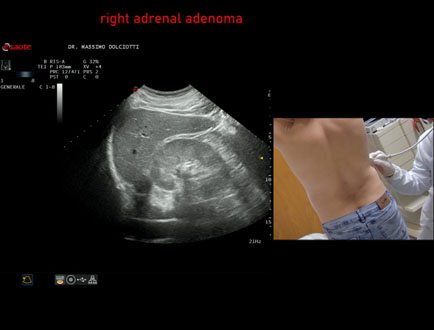

Data inserimento: 22/04/2026

Ecografia del: 03/04/2026

Strumento: Esaote MyLab Eight

Sonda: Convex Multifrequenza 1-8 MHz

Età Paziente: M 49 anni

Motivazione dell'esame: riscontro occasionale

Commento all'esame: le immagini ed il video documentano in regione surrenalica destra, formazione ipoecogena a margini definiti, da ricondurre, come prima ipotesi, ad adenoma surrenalico.

Conclusioni: adenoma surrenalico destro (right adrenal adenoma).

In collaborazione: Dr.ssa Marica Manfredi - Ancona, Dr. Ilir Qose - Ancona

Presentazione: Dr. Massimo Dolciotti - Ancona